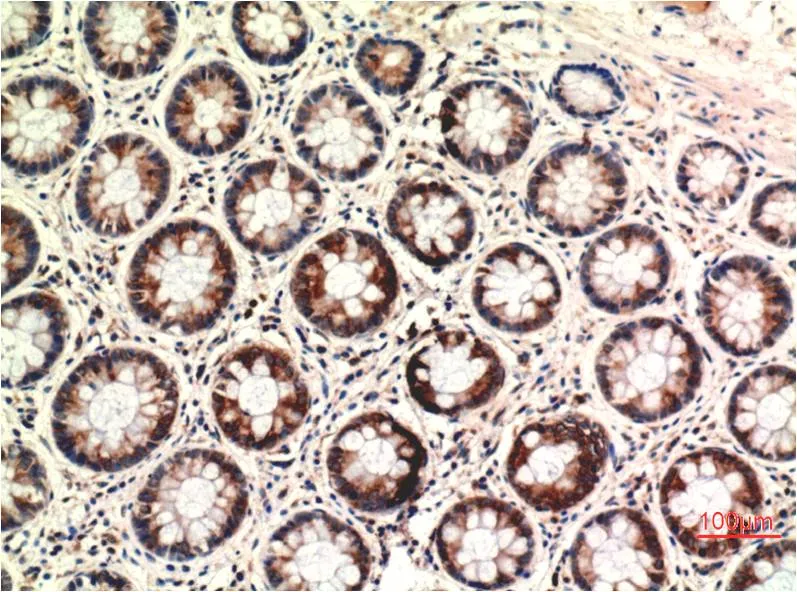

Ki67 (10B6) Mouse Monoclonal Antibody

Cat: AMM00719

Size1:50μl Price1:$150

Size2:100μl Price2:$280

Size3:500μl Price3:$1200

Size2:100μl Price2:$280

Size3:500μl Price3:$1200